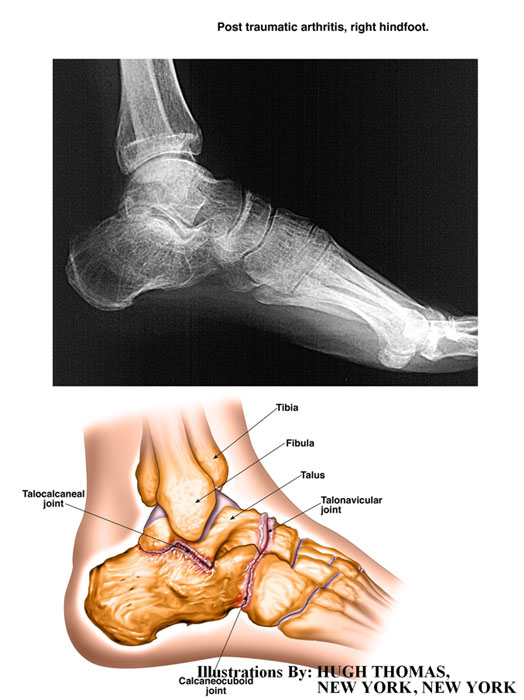

The medical illustrations on this page are examples of the details the attorneys at the Law Offices of William Cafaro prepare for jury presentations.